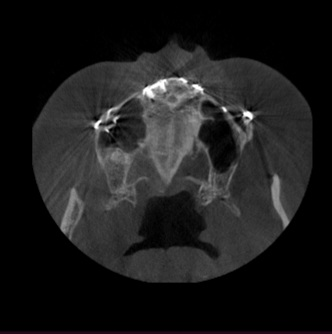

혹시 CT보면 아실수 있을까요?

부비동염인가, 상악동염인가

지금 캡쳐는 예전 ct예요, 2015년이요.

2014년에 얼굴 수술을 하면서 우측 부비동염이 크게 왔어서

마지막 CT사진상으로는 상악동염이잇을정도로 보이진 않습니다. 비염이 있으신경우 비염이 심할때 상악동에 일시적으로 염증이 생길수는 있습니다. 예전 사진으로는 상악동염은 아닌거 같습니다.

일단은 상악동염, 부비동염 정도를 일으킬 정도의 염증은 아닙니다. 만성적으로 비염이 있거나 축농증이 있을 때 정도의 염증이 있거나 일부 부위에는 염증이 없습니다. 만약에 상악동염이나 부비동염이라면 이정도가 아니라 육안으로 보더라도 확실히 염증이 보입니다. ct 사진이 과거 자료이기는 하나 과거 자료를 토대로 판단했을 때는 상악동염과 부비동염은 아닌 것으로 보여집니다.